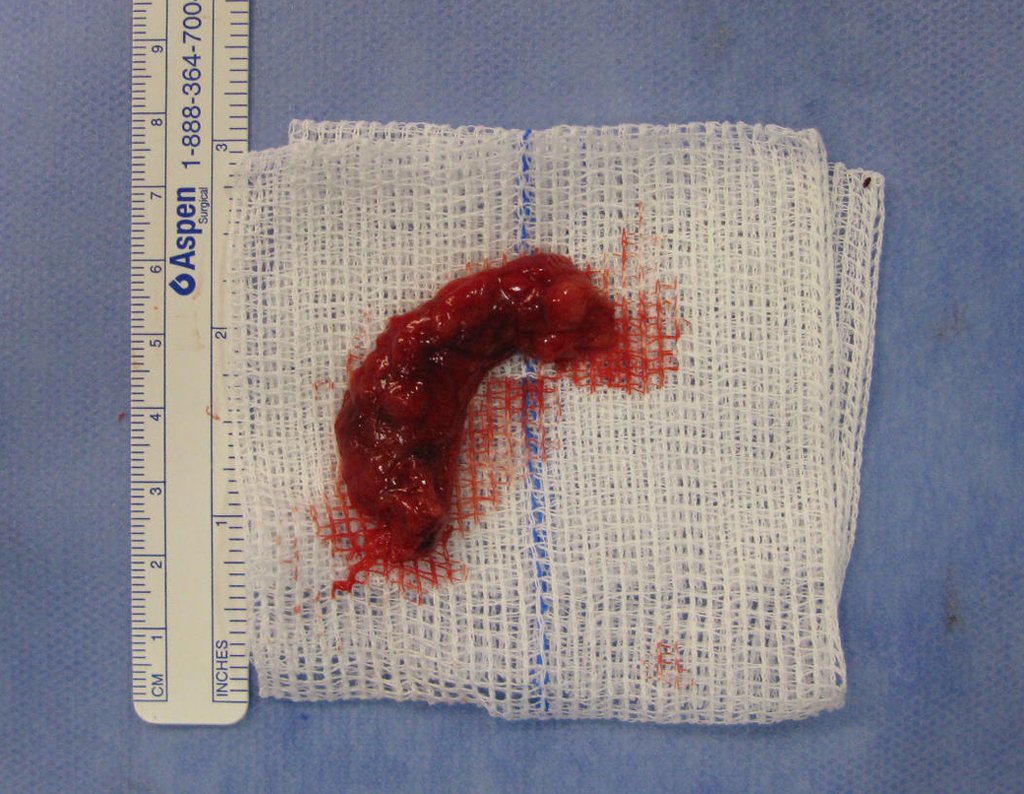

Treatment of bone metastasis from hypernephroma generally involves a multidisciplinary approach, including surgery, radiotherapy, targeted therapy, and/or immunotherapy. The aim of treatment is to control the spread of cancer, alleviate symptoms and improve the patient’s quality of life.